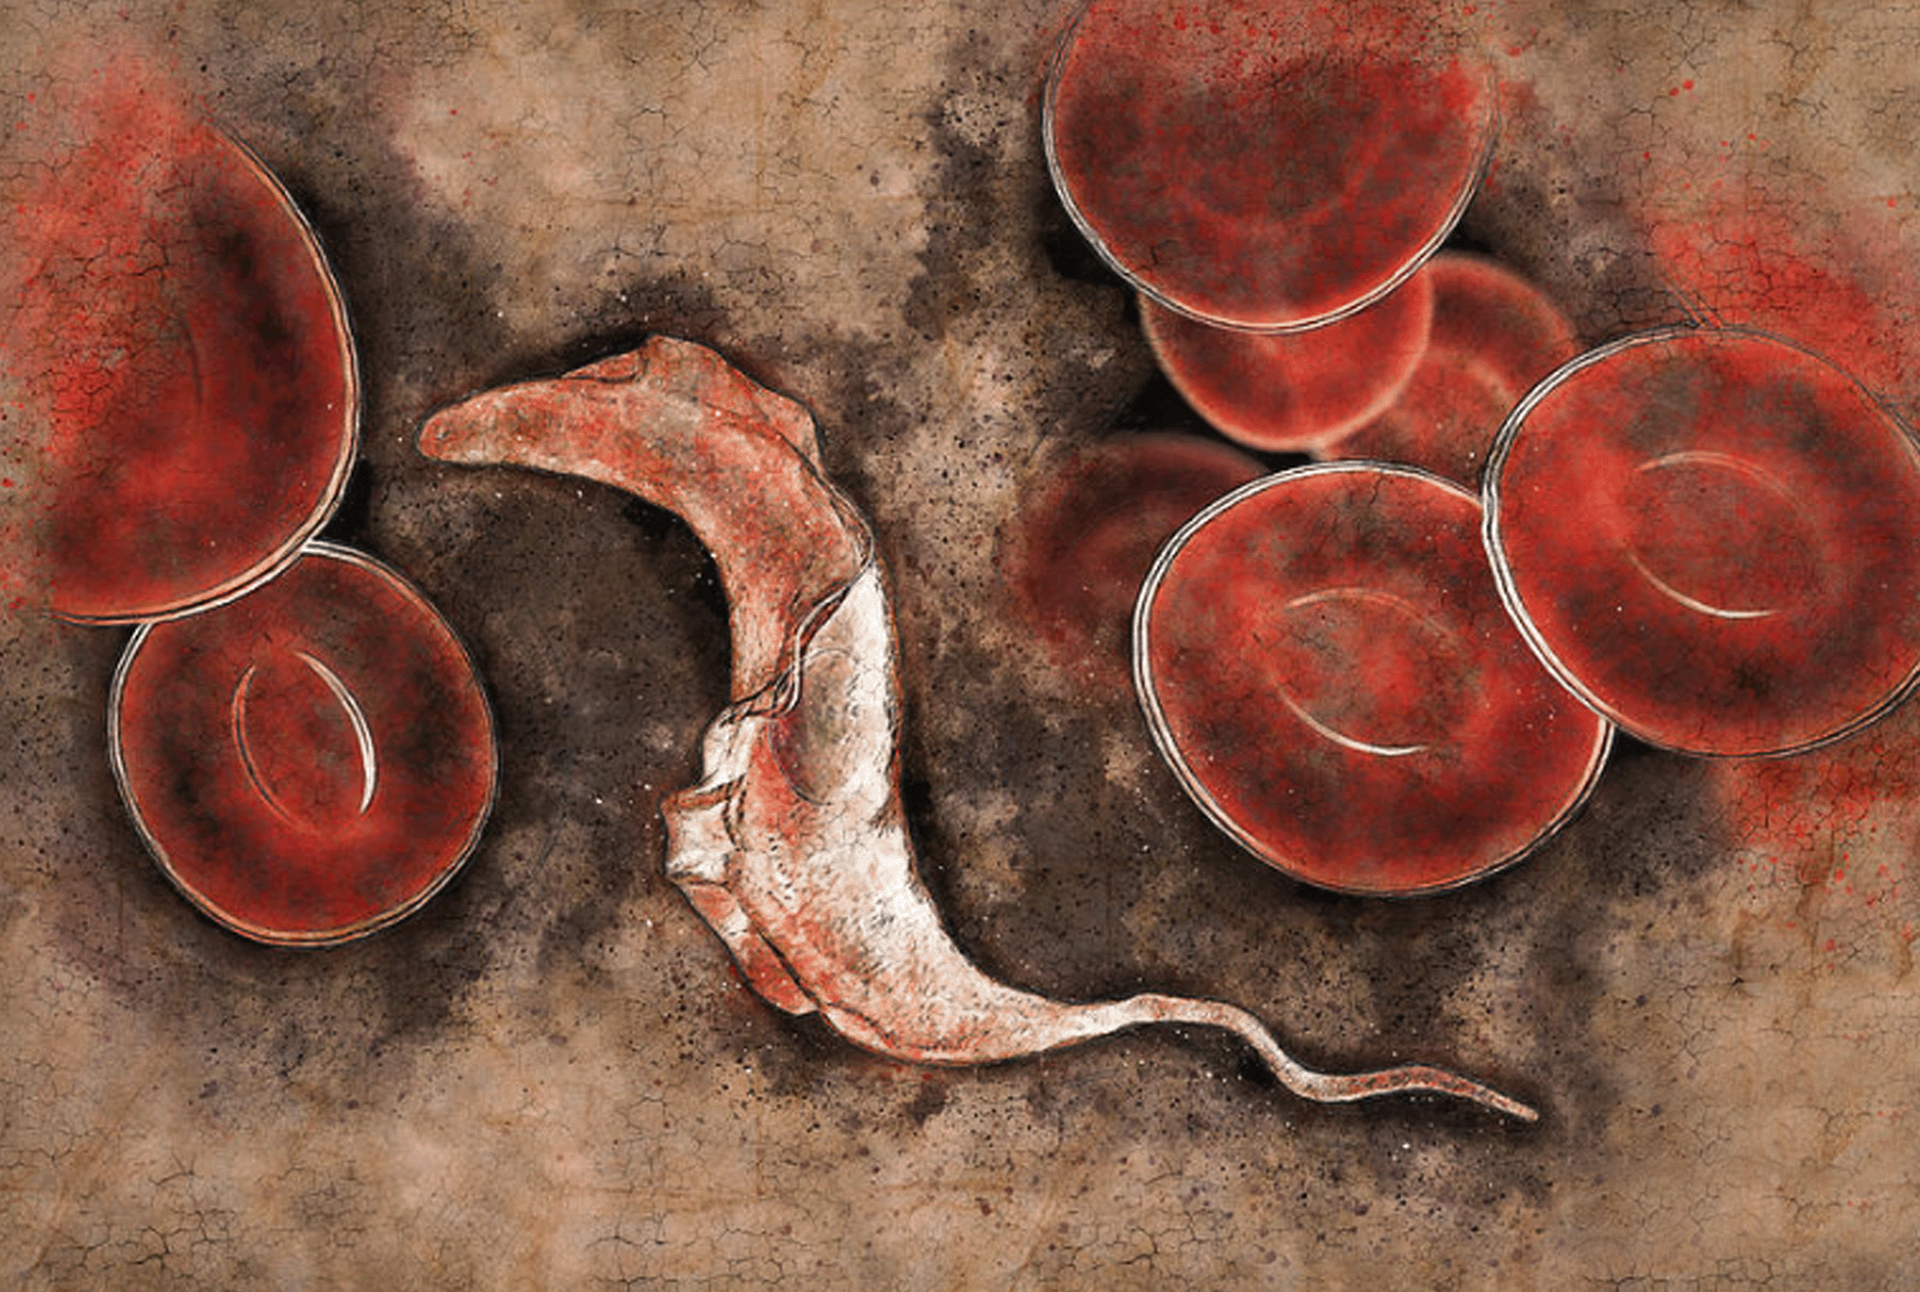

Lutte contre la maladie de Chagas :

détection précoce et soins tout au long de la vie

En 2024, nous braquons les projecteurs sur la maladie de Chagas et les souffrances qu’elle cause, et nous appelons à rendre équitable l’accès aux soins et aux services de santé pour toutes les personnes touchées par la maladie.

Le thème choisi pour 2024 est le suivant : « Lutte contre la maladie de Chagas : détection précoce et soins tout au long de la vie ». L’objectif est de sensibiliser le grand public à la maladie de Chagas et d’obtenir davantage de financements et un soutien accru pour les initiatives visant à diagnostiquer la maladie de façon précoce et à assurer une surveillance post-thérapeutique exhaustive.

La maladie de Chagas est répandue dans les populations pauvres d’Amérique latine continentale, mais elle est également de plus en plus souvent détectée dans d’autres pays et continents.

Elle est souvent qualifiée de « maladie silencieuse et muselée », car la majorité des personnes infectées ne présentent aucun symptôme ou des symptômes extrêmement bénins. Environ 6 à 7 millions de personnes sont infectées par la maladie de Chagas à l’échelle mondiale et on comptabilise 10 000 décès chaque année.